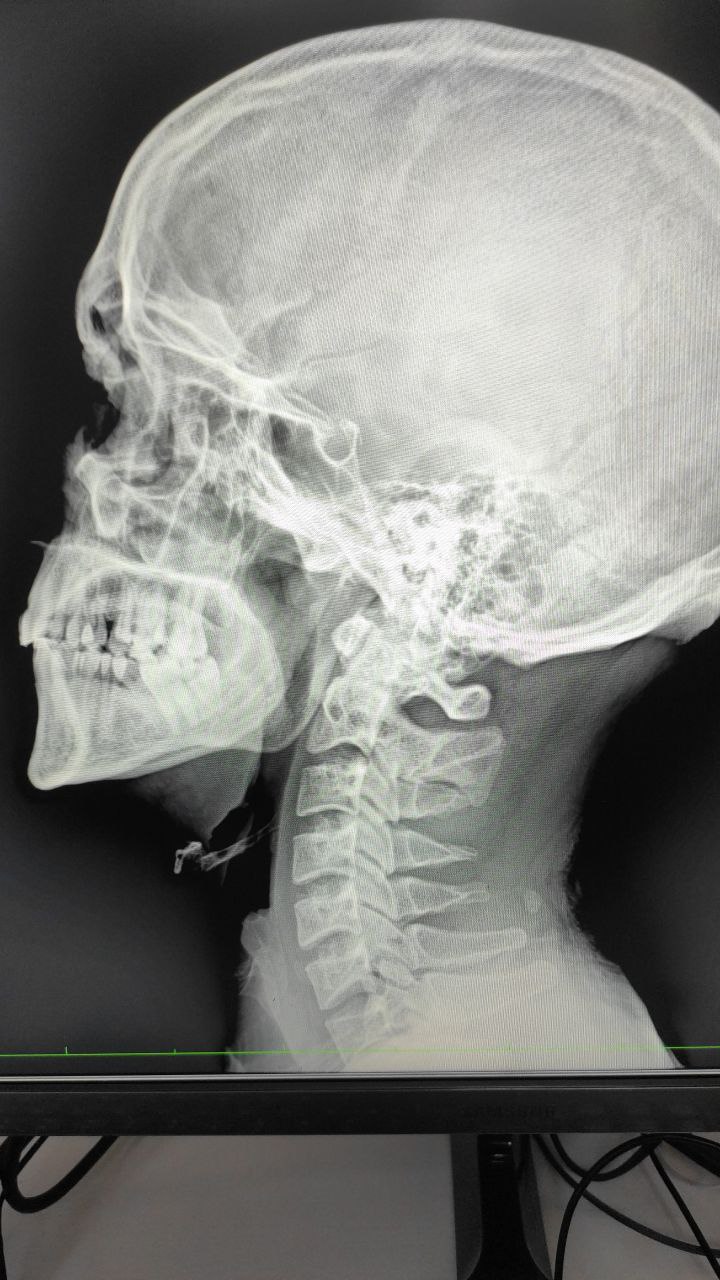

Jahongirshoh in Radiology/Рентгенология Чат

Tohtasin Abdukarimov

Шейных 2 3 патология есть или?

Normalni